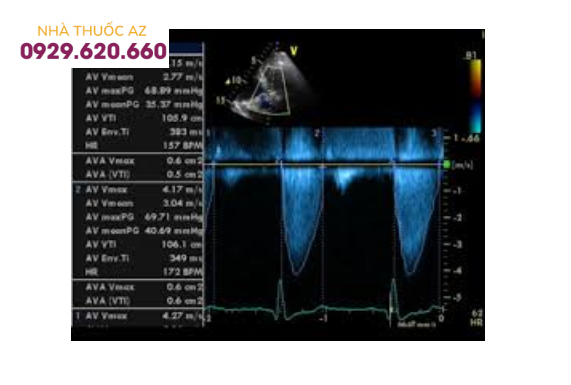

Phổ Doppler liên tục của hẹp nặng van động mạch chủ